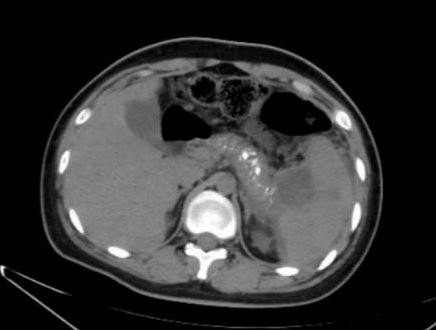

1 资料与方法患者男,17岁,主因“反复腹痛2年,加重伴发热2 d”来诊。患者于2019年起常于进食后出现腹部不适、纳差、腹痛,服用“胃药”对症处理后可好转,此后反复发作,频繁时半月发作一次。2020年9月下旬患者进食油腻食物后出现脐周及左中腹部胀痛,无恶心、呕吐,当地医院腹部CT提示:慢性胰腺炎急性发作,经对症治疗后2~3 d好转,此后每月有类似症状发作一次。2021年1月18日到本院基本外科门诊查胰腺功能,血清淀粉酶73 U/L,脂质624 U/L; 血钙正常; 血脂4项正常; 检查肿瘤指标,CA-125: 46.9 U/mL(升高),余为阴性; 甲状旁腺素正常; 血清IgG四项:IgG3 154 mg/L(降低),IgG4 1 600 mg/L(升高)。腹盆CT示胰腺多发钙化,胰尾囊肿形成(图 1)。1月22日患者进食汤面后出现腹部不适、纳差、乏力。1月24日晨起后出现腹部剧烈疼痛,伴发热,最高37.6℃,无恶心呕吐,无腹泻,于本院急诊就诊查血象正常,超敏C反应蛋白142.15 mg/L,胰腺功能:血清淀粉酶130 U/L, 脂质1 127 U/L。行腹盆CT检查示:胰腺饱满伴多发钙化,胰周脂肪密度稍增高,可见多发索条影,符合慢性胰腺炎改变(图 2)。予厄他培南抗感染及抑酸、补液等支持治疗后症状略好转,于1月26日收入本院急诊留观继续治疗。既往史:早产儿(32周),右桡骨小头骨纤维瘤术后,过敏性哮喘。个人史:否认饮酒史。家族史:父母体健,无其他特殊情况。

| 图 1 患者2021-01-19腹部CT |